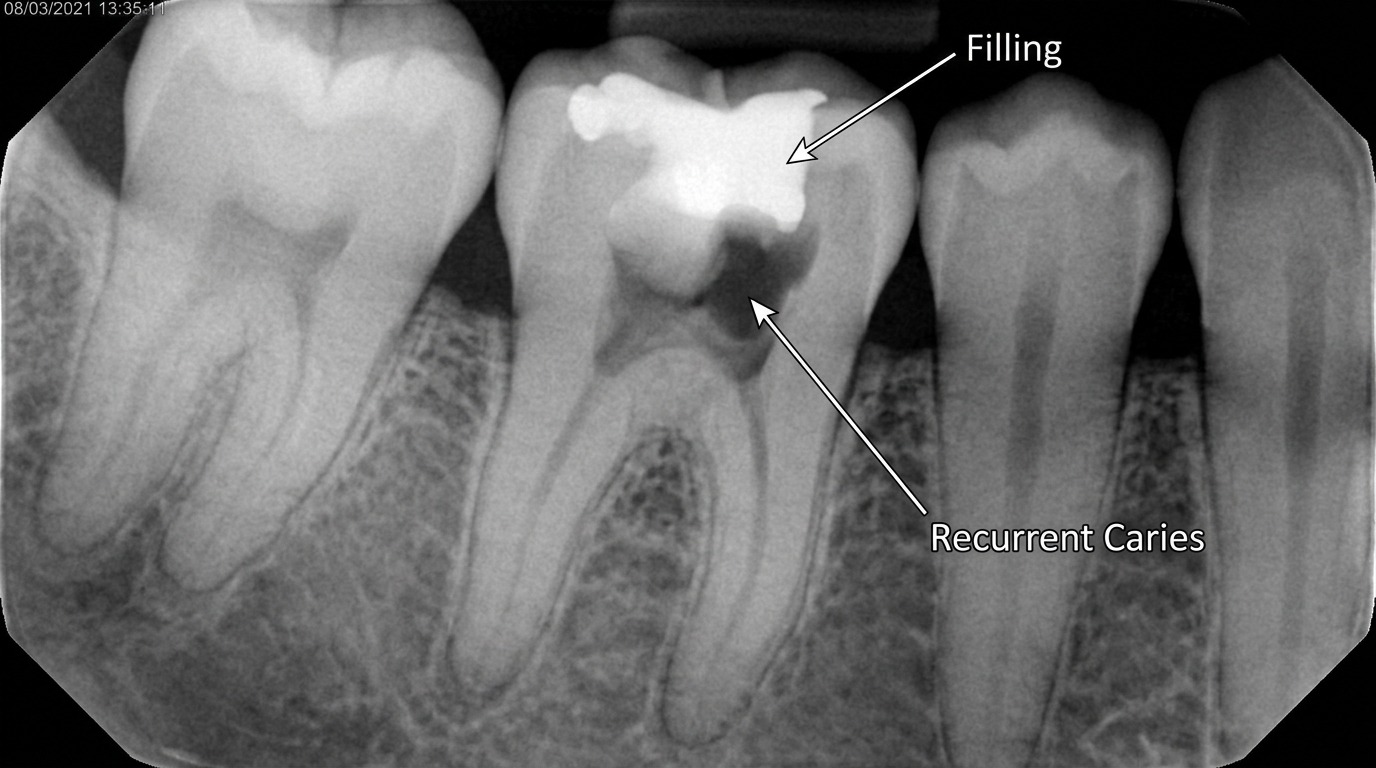

Ząb może wyglądać pozornie dobrze, a próchnica może już rozwijać się stopniowo na granicy materiału i tkanek zęba. Właśnie dlatego regularne kontrole są tak ważne.

Nieszczelna plomba najczęściej nie przylega już szczelnie do zęba, przez co między wypełnieniem a tkanką zęba powstaje mikroszczelina. Do środka mogą dostawać się ślina, bakterie i resztki pokarmu, co sprzyja nadwrażliwości, przebarwieniom i próchnicy wtórnej pod plombą.

Do rozszczelnienia plomby dochodzi najczęściej w wyniku procesów próchniczych toczących się pod materiałem, naturalnego zużycia materiału lub uszkodzeń mechanicznych. Nieszczelność powoduje powstawanie mikroszczelin między plombą a tkanką zęba, co umożliwia dostęp bakteriom.

• próchnicę wtórną

Najczęściej konieczne jest usunięcie starego wypełnienia, oczyszczenie zęba i sprawdzenie, w jakim stanie są jego tkanki. Jeśli pod plombą rozwinęła się próchnica wtórna albo uszkodzenie jest głębsze, zakres leczenia może być większy niż sama wymiana wypełnienia.